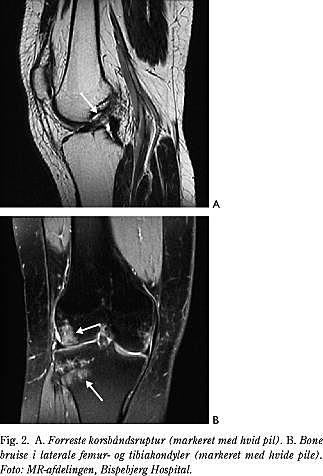

Artroskopisk synlige bruskskader ses hos ca. 10%, men ved MR-scanning kan der hos over 50% påvises et kraftigt knogleødem (bone bruise) i den laterale femurkondyl i månederne efter en korsbåndsskade (Fig. 2), og biopsier tyder på, at forandringerne når helt ned i brusken. Det vides ikke, om bone bruise disponerer for slidgigt, men det kan være årsagen til, at nogle patienter har meget ondt, når de støtter på knæet i månederne efter en korsbåndsskade.

• afrivning af det forreste korsbånd med et knoglestykke fra eminentia tibiae (Fig. 3),